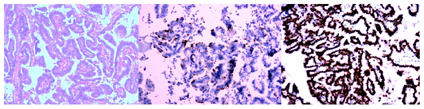

术后左侧甲状腺病理检查提示:左侧甲状腺乳头状癌,肿瘤直径4 mm,癌组织侵犯被膜脂肪组织;左侧颈部Ⅳ区肿块病理检示:左侧颈部异位甲状腺乳头状癌;癌组织侵犯被膜脂肪组织,并且癌组织侵犯颈内静脉及神经纤维。免疫组化肿瘤细胞呈:CK7(+),CK20(-),CEA(-)、TTF-1(+)、TG(+)、CK19(+)、HBME(+)、CycLinD(+)/CD5(-)/Ki-67(20%+)(图3)。左侧颈侧区及左侧中央区部分淋巴结未见癌转移。术后接受TSH抑制治疗,每日服用优甲乐50μg,目前电话随访(2次/月),患者病情稳定,无复发或转移。